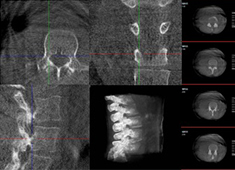

機(jī)器人做胸椎手術(shù)怎么樣:經(jīng)皮釘棒系統(tǒng)內(nèi)固定術(shù)案例分享

使用骨科手術(shù)機(jī)器人做胸椎手術(shù)的效果怎么樣?今天普愛醫(yī)療分享一則臨床案例——經(jīng)皮釘棒系統(tǒng)內(nèi)固定術(shù),看看普愛手術(shù)機(jī)器人如何助力手術(shù)順利進(jìn)行。...